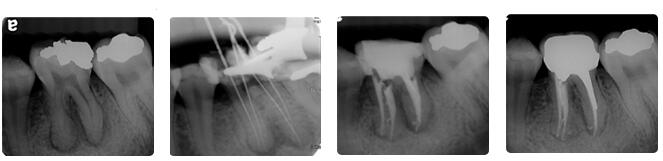

根管治疗通常包括三个基本步骤:根管预备、根管消毒、根管充填。

首先会解决根管内的炎症牙髓和坏死物质,接下来测量根管长度,并适当扩大根管(即根管预备过程),然后在根管内封药消毒, 用药物充填根管。

根管治疗时,拍牙片是很有必要的,并且至少要确保3张牙片。

第一张在治疗前,帮助医生了解牙根的基本情况,制定治疗计划;

第二张在治疗中,帮助医生了解治疗情况,如根管预备是否到位等,并制定下一步治疗方案;

第三张是在治疗结束后,帮助判定根管充填质量,发现问题及时补救。